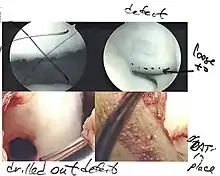

Intact lesions

If non-surgical measures are unsuccessful, drilling may be considered to stimulate healing of the subchondral bone. Arthroscopic drilling may be performed by using an antegrade (from the front) approach from the joint space through the articular cartilage, or by using a retrograde (from behind) approach through the bone outside of the joint to avoid penetration of the articular cartilage. This has proven successful with positive results at one-year follow-up with antegrade drilling in nine out of eleven teenagers with the juvenile form of OCD,[53] and in 18 of 20 skeletally immature people (follow-up of five years) who had failed prior conservative programs.[54]